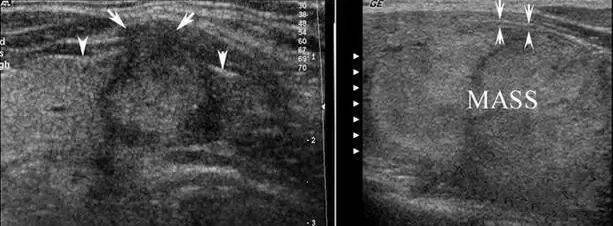

左图:乳头状癌患者,中间两个箭头所指处癌灶已突破甲状腺被膜侵犯颈前肌,外侧两个箭头指向正常甲状腺被膜,其间的正常高回声带(甲状腺被膜)中断。

右图:腺瘤(MASS)虽然很大,但其包膜(指向上方的箭头)与甲状腺被膜(指向下方的箭头)清晰可见,甲状腺被膜无明显中断,反映肿瘤没有侵犯甲状腺被膜。